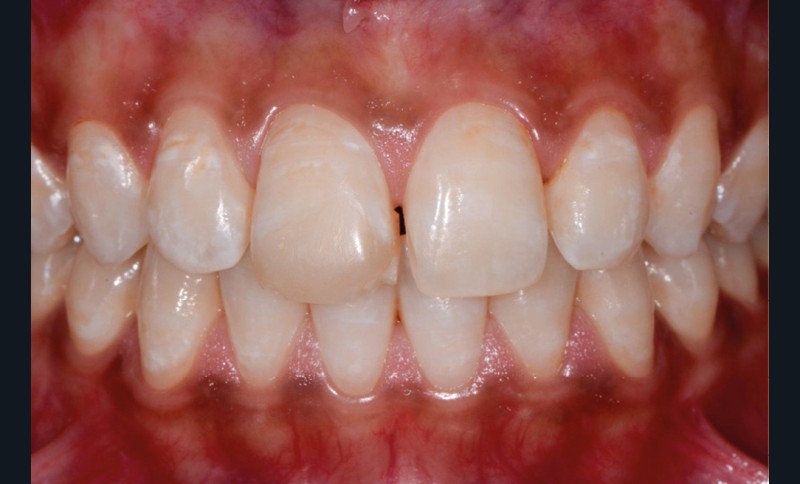

Elles sont causées par des agents colorants externes qui se déposent généralement sur la surface amélaire. Leurs origines sont diverses : alimentation (fig. 1b), tabac (fig. 1c), plaque bactérienne ou bactéries chromogènes (fig. 1d), ainsi que certains médicaments. La réalisation d’un aéropolissage en complément du détartrage initial est généralement suffisante pour éliminer efficacement ces colorations. Cependant, le patient doit être prévenu qu’en l’absence de modification de ses habitudes de vie, celles-ci reviendront [2, 4].